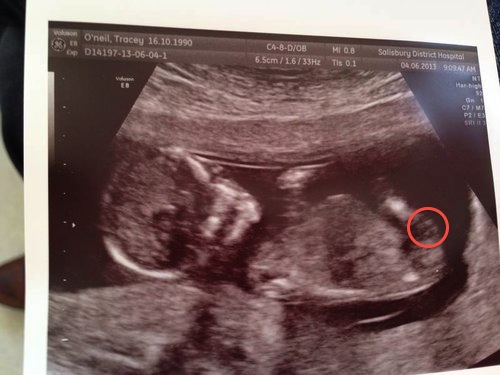

Please could you have a guess at the gender of my little bean please??

i think boy

Sorry I can't see any gender clues.....congrats on baby tho :)

No nub clues but going with girl on the skull.

The nub appears as my ds2's did... i'll try and circle what i see... hang on

Thanks Deaks, i didnt even realise that was the nub i thoguht that was part of babies leg!

Could still be leg but it kinda looks nubish to me and is in right spot. Hopefully youll get some more guesses!

I really think that's part of the leg and that's to big for being a nub. Maybe just under the lines you have circled you might see a hint of a girly nub.